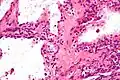

![]() Micrografía mostrando un cistoadenoma seroso del páncreas. H&E stain. | ||

El cistoadenoma seroso del páncreas es un tumor benigno de este órgano. Generalmente se encuentra en la cola del páncreas,[1] y puede estar asociado con el síndrome de von Hippel-Lindau.[2]

En contraste con algunos de los otros tumores del páncreas que forman quistes (como la neoplasia mucinosa papilar intraductal y la neoplasia quística mucinosa), las neoplasias quísticas serosas son casi siempre completamente benignas. Hay algunas excepciones; en raras ocasiones, se han descrito casos de cistoadenocarcinomas serosos malignos aislados.[3] Además, las neoplasias quísticas serosas crecen lentamente y, si crecen lo suficiente, pueden presionar los órganos adyacentes y causar síntomas.